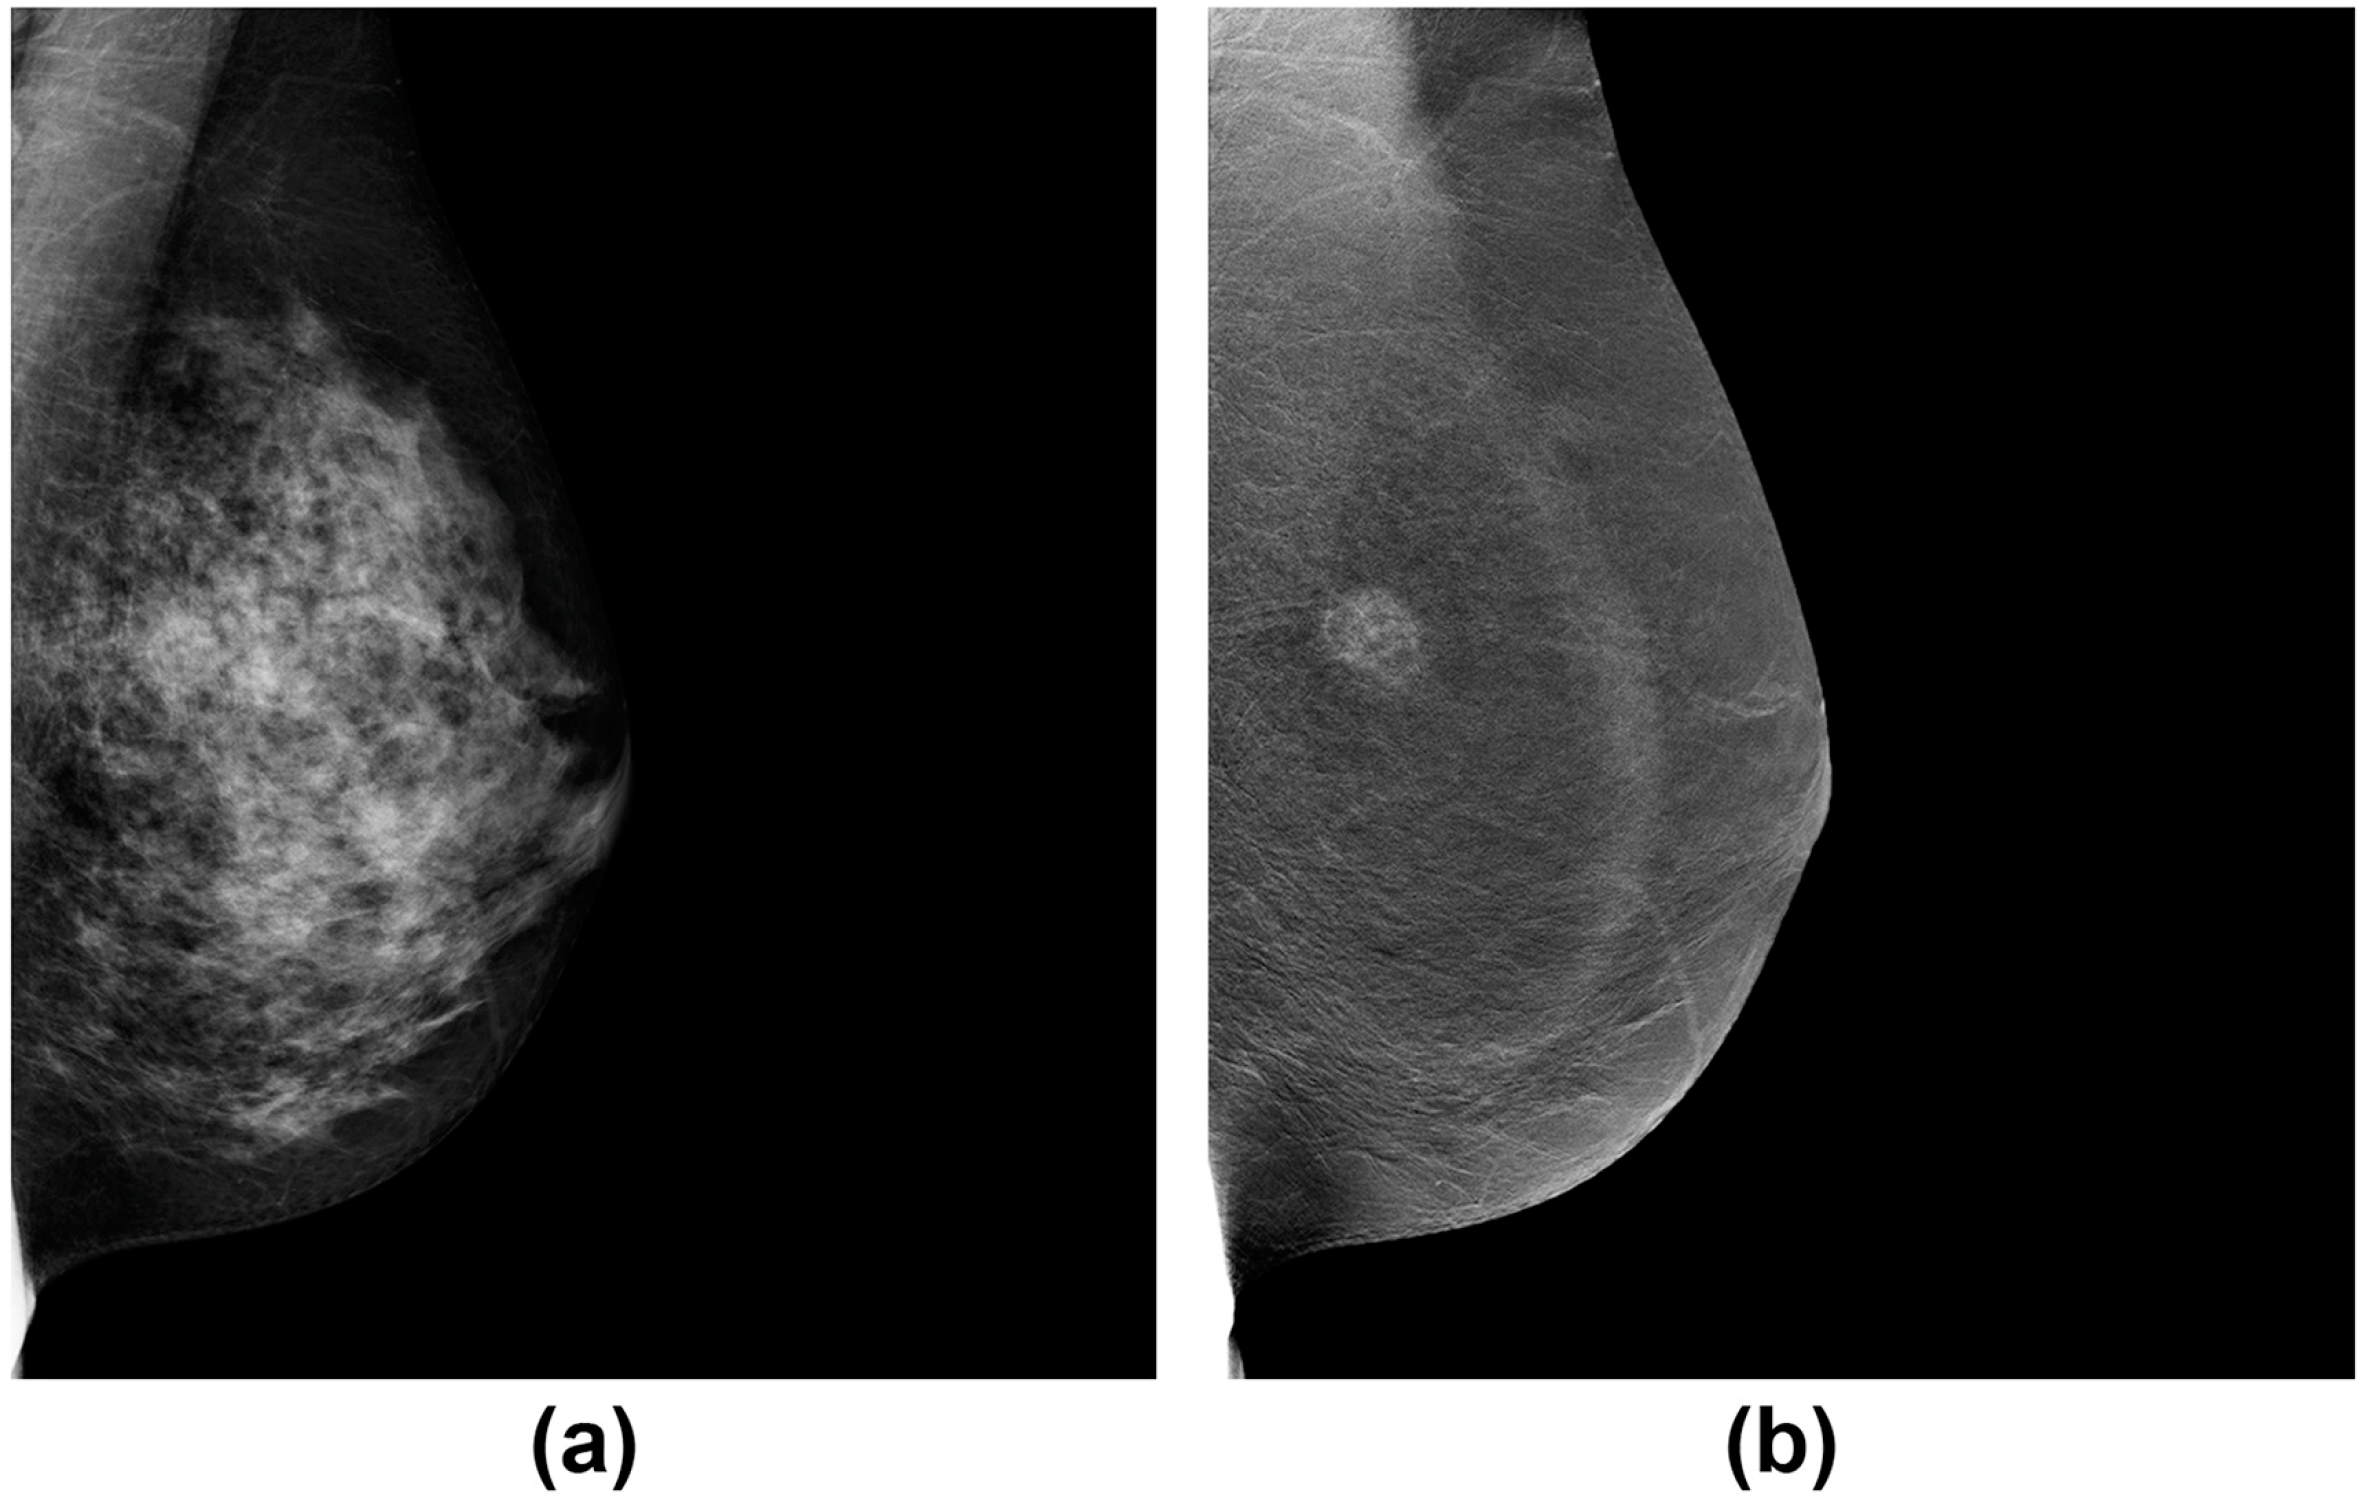

Фиброаденома молочной железы - доброкачественное образование, которое часто встречается у женщин. Оно может быть обнаружено при помощи различных методов диагностики, включая маммографию. Ниже представлены фотографии, помогающие понять, как выглядит данное заболевание.

Маммография и ее роль в диагностике фиброаденомы молочной железы

Маммография - это рентгенологическое исследование молочных желез. Оно позволяет выявить различные изменения в тканях, включая фиброаденому. На маммограммах можно увидеть структурные особенности опухоли и отследить ее динамику во времени.